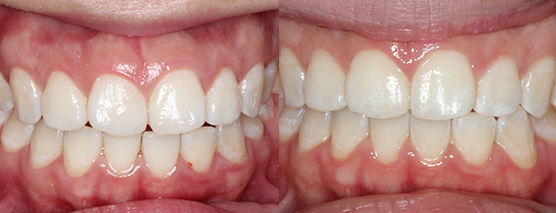

Case examples that can be treated in your practice.

(Cases treated by Dr Andrew Chang using in office aligner solutions)

Before

After